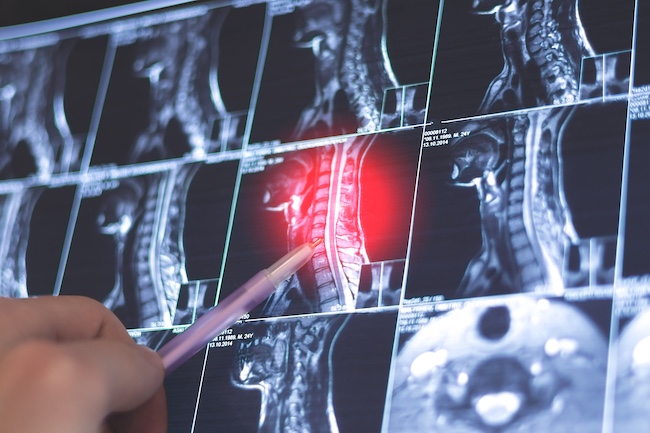

Imaging Studies

To confirm the diagnosis, we use advanced imaging techniques. An MRI provides a detailed view of the cervical spine, including soft tissue, spinal nerves, and discs. It shows whether a cervical disc herniation, bone spur, or spinal canal narrowing is pressing on a nerve root.

X-rays may be used to identify bone alignment or signs of cervical spondylosis. In some cases, a CT scan or CT myelogram is used to get a clearer view of the spinal canal and surrounding structures.